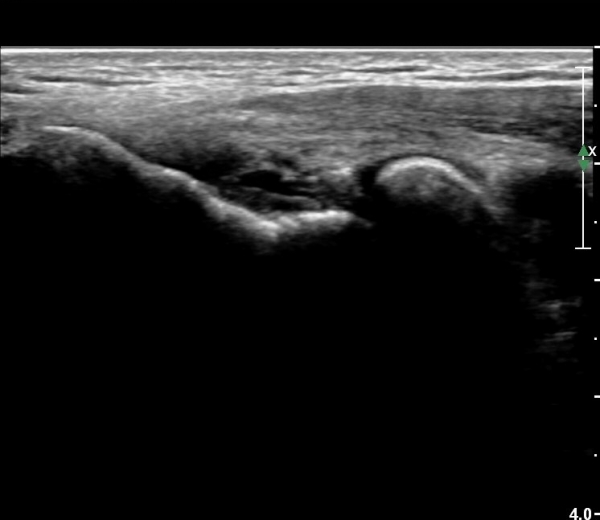

ÃÊÀ½ÆÄ °Ë»ç

ÆÈ²ÞÄ¡ ¾ÕÂÊ ¼ÒµÎ Á¾´Ü¸é°Ë»ç¿Í Ⱦ´Ü